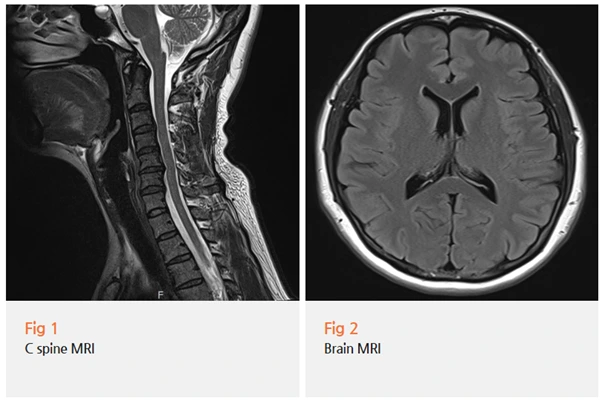

환자분을 설득하여 당일 경추 MRI를 촬영한 결과,

예상이 적중했습니다.

경추 4-5-6번 사이에 협착증이 명확하게 보였어요.

뇌 MRI에서는 특별한 문제가 없었고요.

"목이 문제인데 왜 귀가 아프고 어지러운 거예요?"

환자분은 당연히 의아해하셨습니다.